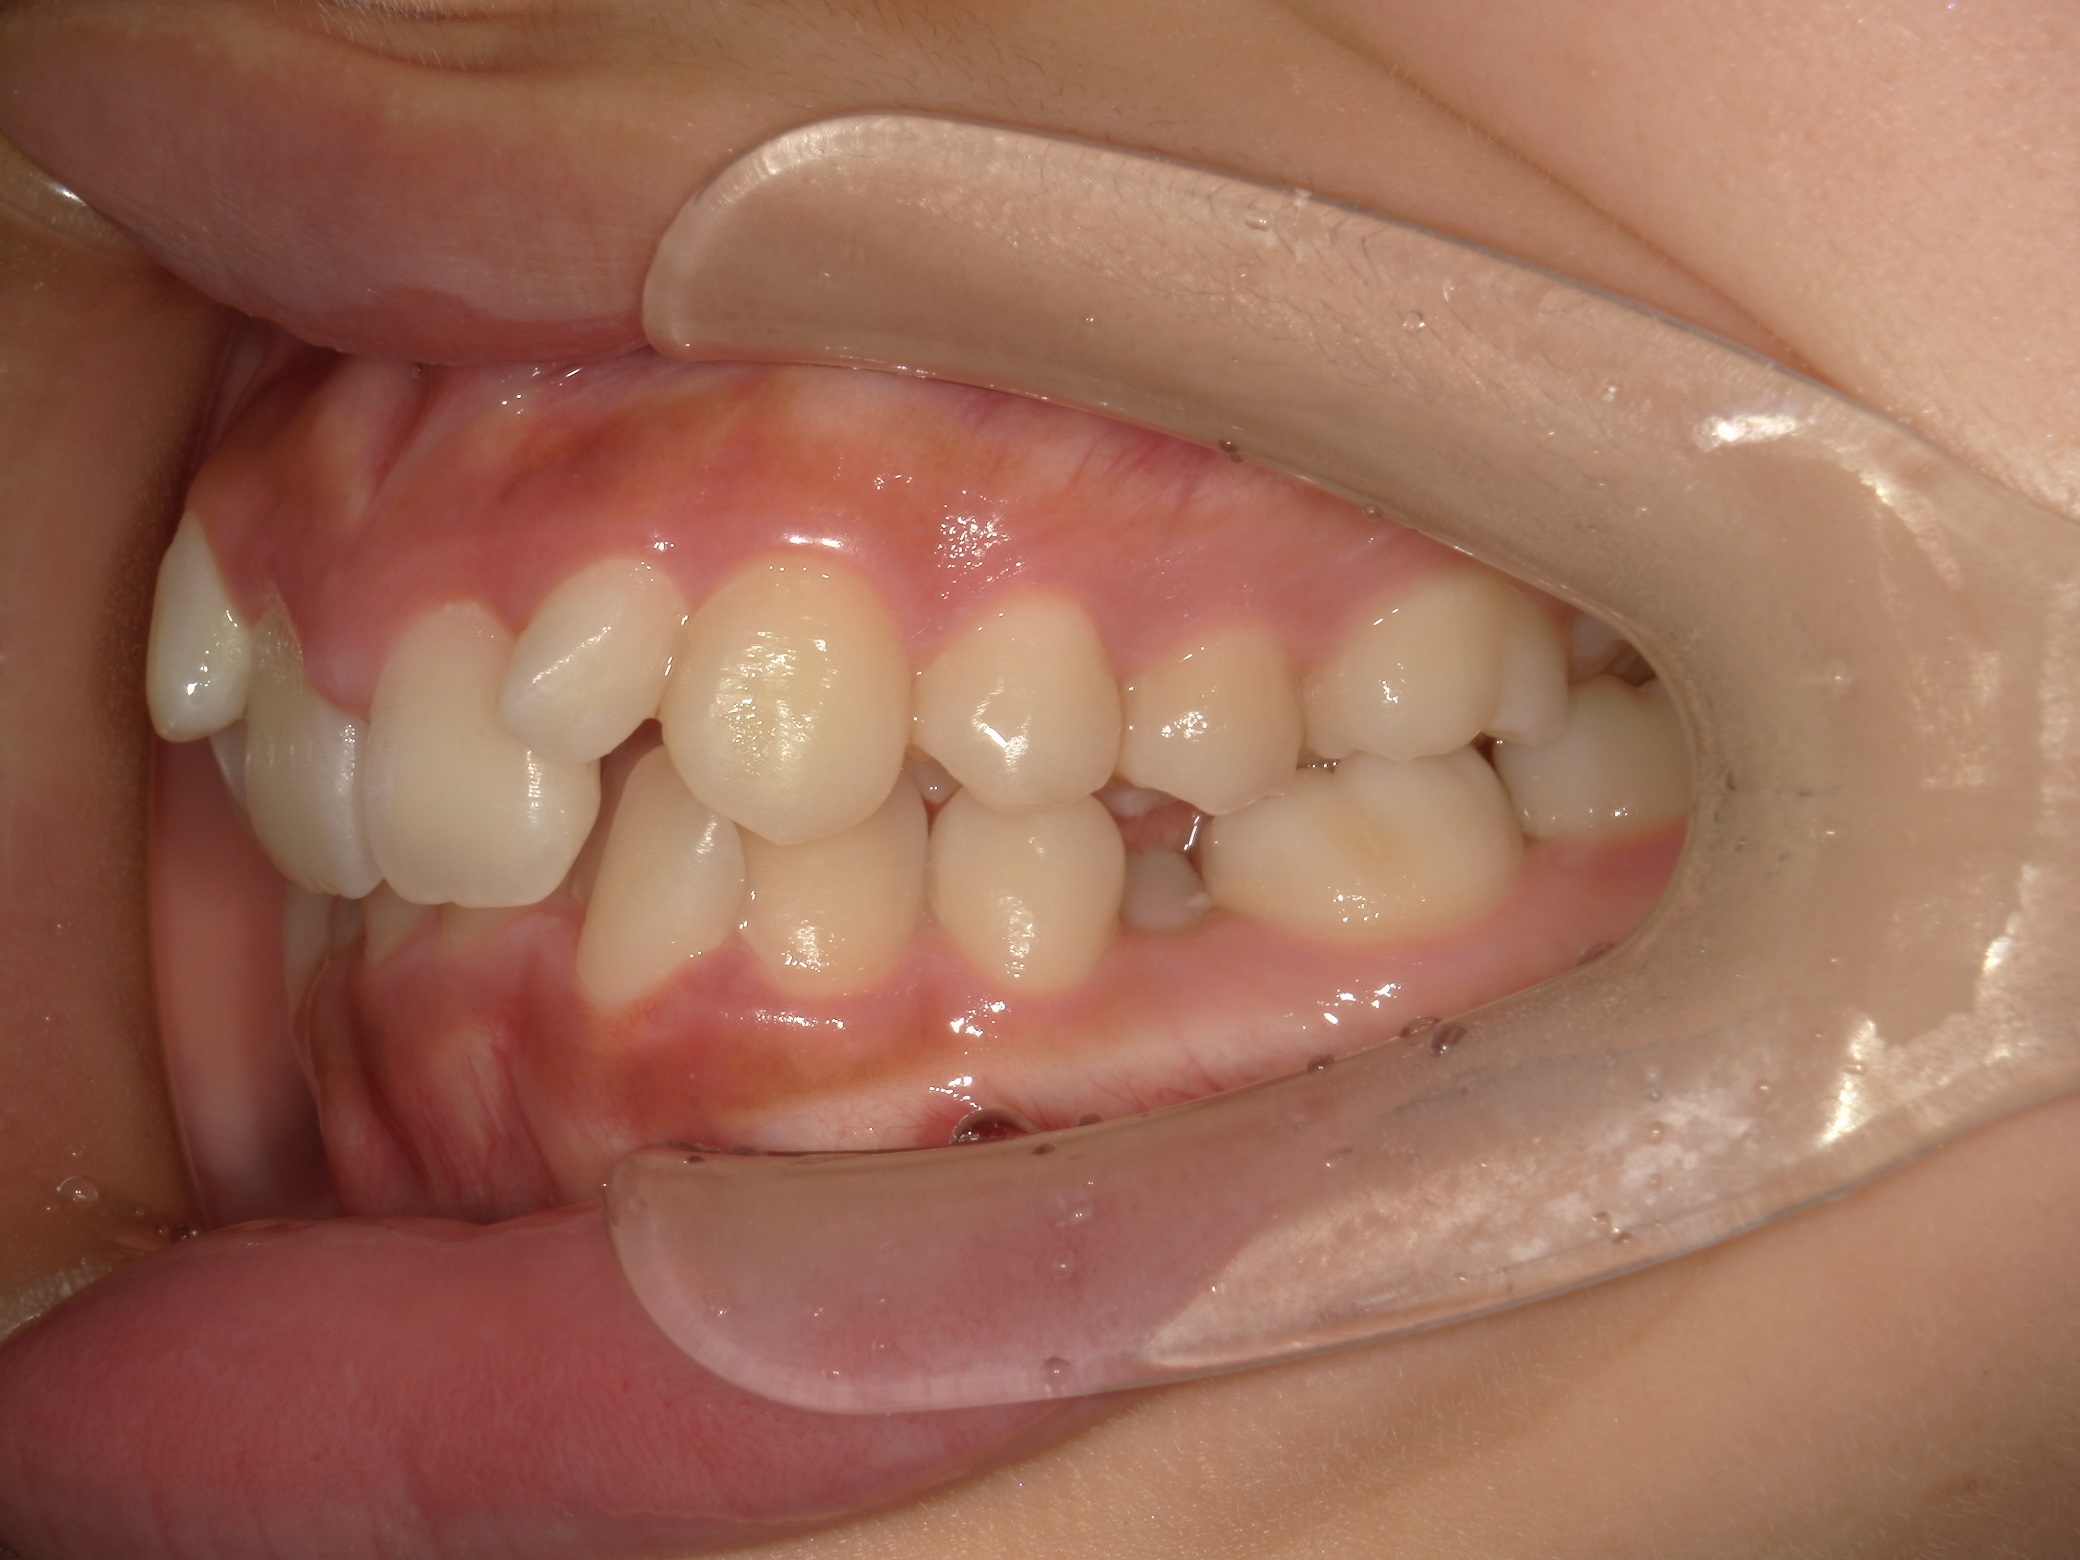

口内下

治療前

歯を並べる隙間を作るため、上下共に歯を抜いて治療を行うこととしました。

上は矮小歯を、下は横の歯を抜いて治療を行いました。